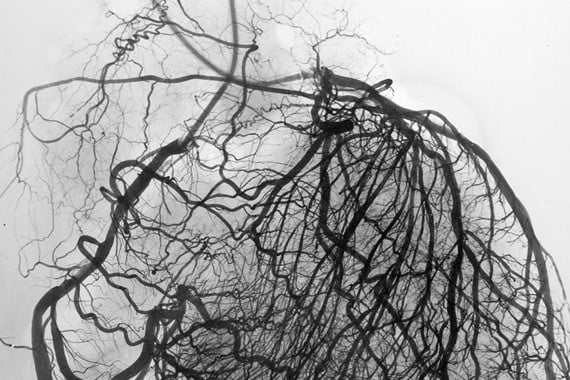

People with suspected coronary heart disease often have an invasive coronary angiogram to make the diagnosis. This is where a catheter is passed into a blood vessel and directed to the heart to take pictures of the coronary arteries. But in two thirds of cases, the angiogram shows no evidence of a blockage in the coronary arteries. This suggests that doctors might be performing the invasive angiogram test too often.